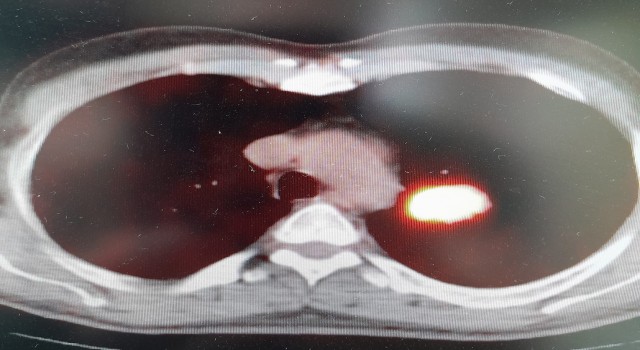

Pandeminin sona ermesi ile toplumu en çok etkileyen, hastaların ve yakınlarının kâbusu olan kanser hastalığı gerçeğine geri döndük. Uzmanlar, bilim ve teknolojide yaşanan gelişmelere rağmen, hala kanser tedavisinde erken tanı koymanın yerini alabilecek bir tedavi yöntemi bulunamadığında hemfikir. Altınbaş Üniversitesi Tıp Fakültesi Göğüs Hastalıkları Bölüm Başkanı Prof. Dr. Şevket Özkaya, “Bugün bilinen en önemli husus, yaşayan her hücrenin sonunun kanser ve ölüm olacağı. Örneğin, bir insanın akciğer kanserine veya meme kanserine yakalanma yaşı genetik olarak kodlanmıştır. Tıp dünyası eğer bir insan, başka hastalıklardan hayatını kaybetmeyip, 150 veya 170 yaşına kadar yaşarsa mutlaka kanser hastası olacağını öngörüyor” diyerek çarpıcı bir iddia da bulundu.

“Kanser” nasıl daha erken ortaya çıkıyor?

Prof. Dr. Şevket Özkaya, yaptığı değerlendirmeyle önemli uyarılarda bulunarak, “Eğer sigara kullanıyor veya kanserojen maddelere maruz kalıyorsanız, bu kansere yakalanma yaşınızı düşüren bir faktör. Örneğin; 150 veya 170 yaşında akciğer kanseri olacak bir kişi, sigara içtiği için bu yaş 100’e düşüyor. Eğer ailede kanser öyküsü varsa bu yaş daha da düşüyor. Ve 45 yaşından sonra her an kanser gelişmesi ile karşı karşıya kalınıyor” diye konuştu. Bu durumda kişiyi kanserden kurtaracak en etkili yöntemin erken tanı ve tedavi olanakları olduğuna dikkat çeken Özkaya, pandeminin kanser konusunda topluma önemli bir katkısı olduğunu anlattı. Covid-19 nedeniyle başvuran hasta sayısında ve radyolojik görüntülemelerde yaşanan artışın birçok vakanın erken evrede saptanmasını sağladığını belirtti.